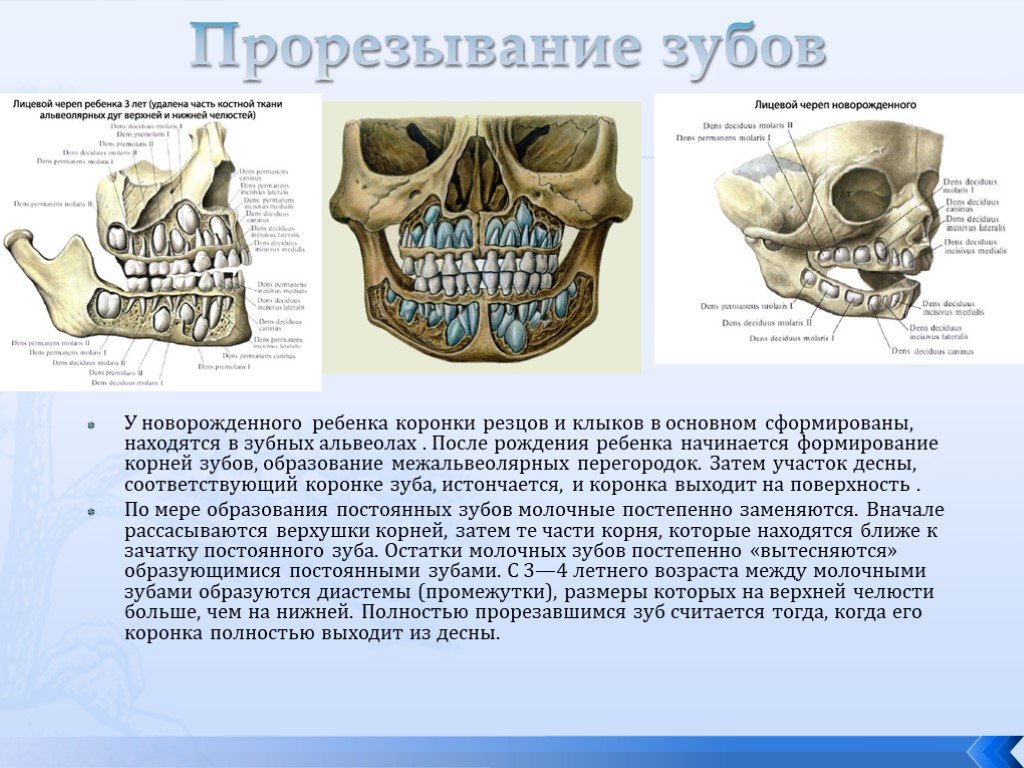

Анатомия детского черепа: Рентгеновские снимки и описание